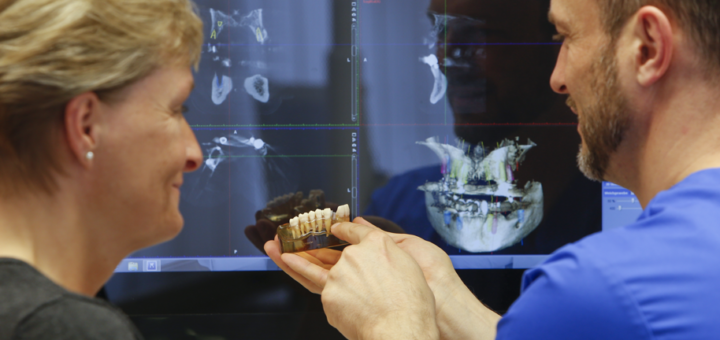

Moderne Zahnmedizin

Die moderne Zahnmedizin bringt Fortschritt und Innovation In den letzten Jahren hat die moderne Zahnmedizin bedeutende Fortschritte gemacht, die das Patientenwohl erheblich verbessern. Von der Diagnostik bis hin zur Behandlung sind innovative Technologien und...

Zahnarzt in Gröbenzell und Umgebung

Bei uns bekommen Sie alle zahnärztlichen Leistungen aus einer Hand In unserer Zahnarztpraxis in Gröbenzell bieten wir Ihnen vielseitige zahnärztliche Leistungen aus einer Hand. Von Implantaten über digitale Volumentomografie (DVT) bis hin zur Endodontie...